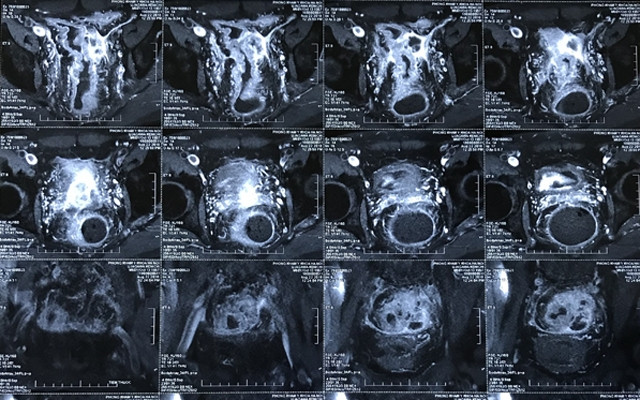

Sau khi làm các xét nghiệm, chụp X-quang, siêu âm, nội soi, bác sĩ Bệnh viện K chẩn đoán ông bị ung thư trực tràng giai đoạn tiến triển. Ngay sau đó phác đồ đa mô thức chuẩn trong điều trị ung thư đại tràng đã được đưa ra cho bệnh nhân. Ông KemlChi được chỉ định điều trị hóa xạ trị tiền phẫu, sau đó sẽ phẫu thuật trực tràng.

Ca phẫu thuật được đánh giá phức tạp bởi khối u tương đối lớn xâm lấn thành chậu, việc phẫu tích gặp nhiều khó khăn, ekip phải thắt mạch máu và chậu trong. Ca phẫu thuật diễn ra thành công, các bác sĩ lấy trọn vẹn được khối u 4x5cm.